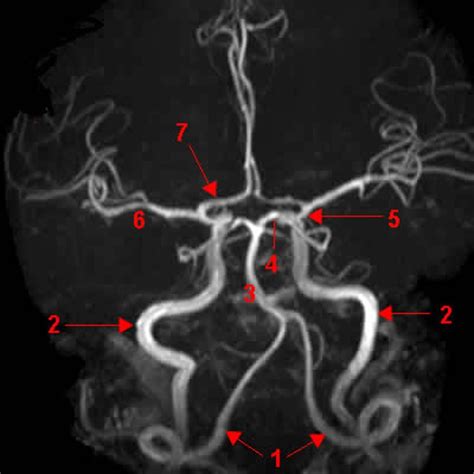

Willis circle mri. . ...

Willis circle mri. .